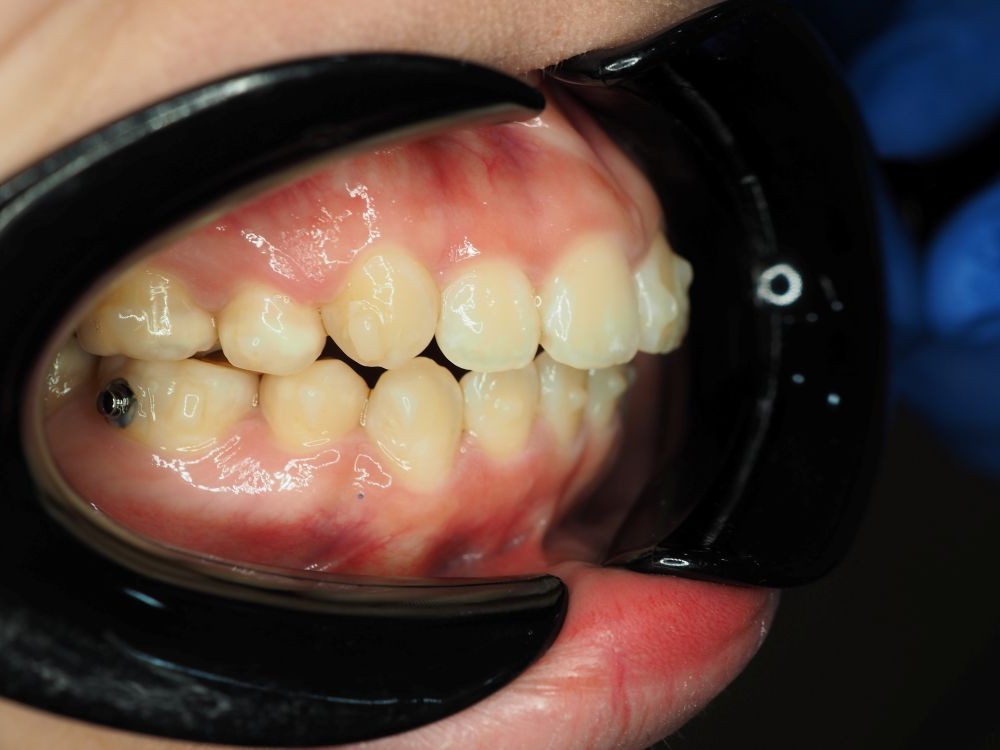

Case Study 2

Upper jaw growth → Corrected reverse bite

Age

9 years old

Parent Concern

“Her lower jaw covering upper jaw, how can Dr help with this?”

Clinical observation

Upper jaw is under-developed.

Treatment Approach

Promote mid face growth (Clear Aligner + facemask)

Treatment Outcomes

Her reverse bite was corrected in just a few months! 😁

Before (March 25)

After (Sep 25)

Actual patient results. Individual outcomes may vary.